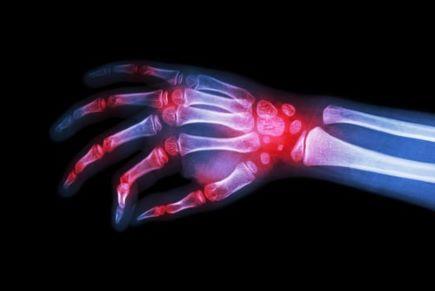

גלוקוזמין סולפאט משמש לטיפול בתסמיני דלקת פרקים ניוונית (osteoarthritis).

טיפול מוקדם בגלוקוזמין סולפאט, החל משלביה המוקדמים של המחלה, עשוי להגן על הסחוס במפרק, להקל על הכאב, להוביל לשיפור בתפקוד ולשפר את איכות החיים.